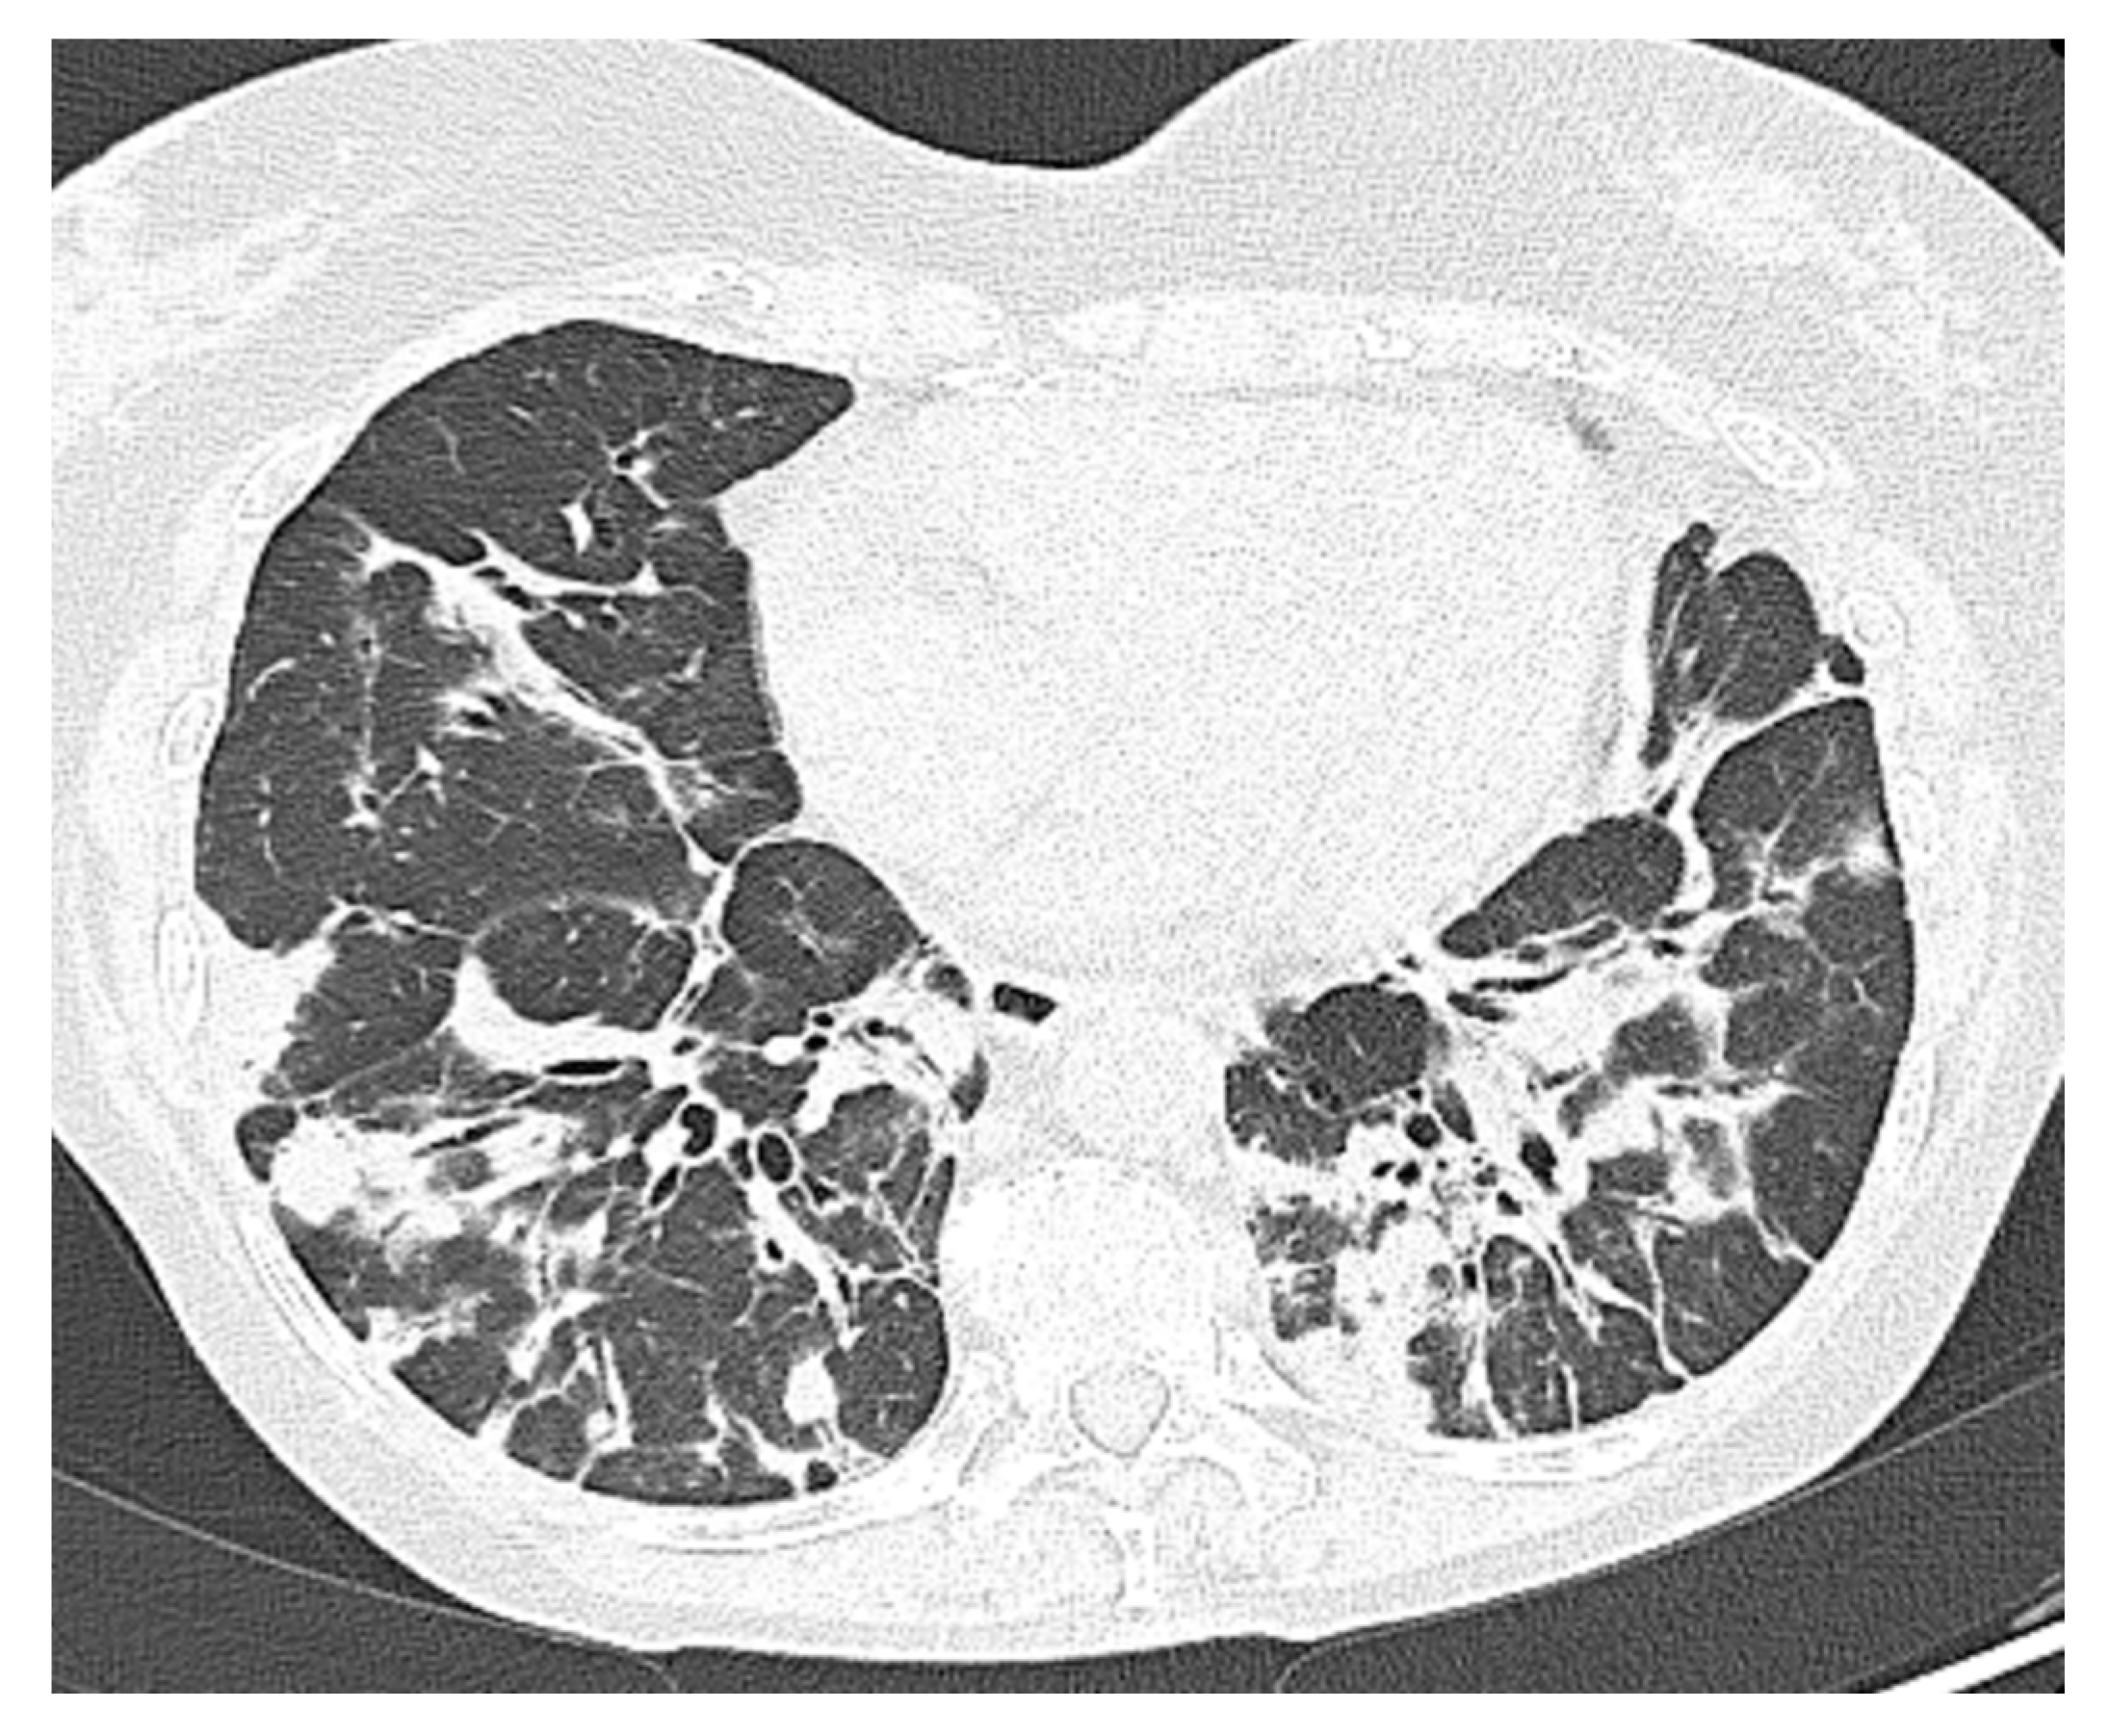

| Comorbidity | RA | Splenomegaly, bronchiectasis; recurrent viral infections | Hypertrophic cardiomyopathy; AF; CKD secondary to nephrolithiasis. C | Bronchiectasis; COPD; EBV-related NHL | GLILD; Bronchiectasis; colonization Aspergillus; Sjogren syndrome; CKD |

| SARS-CoV-2 related pneumonia | yes | yes | yes | yes | no |

| O2 supplementation therapy needed | LFNC | LFNC | HFNC | HFNC | LFNC |